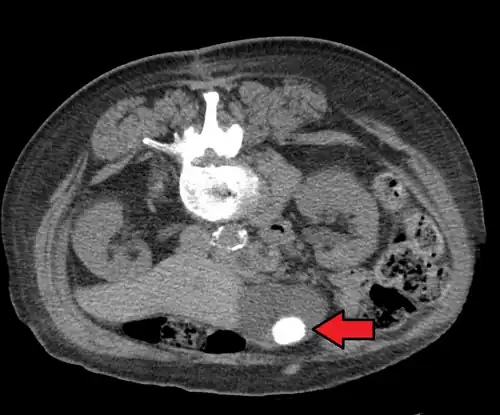

CT images of gallstones

Large gallstone as seen on CT -